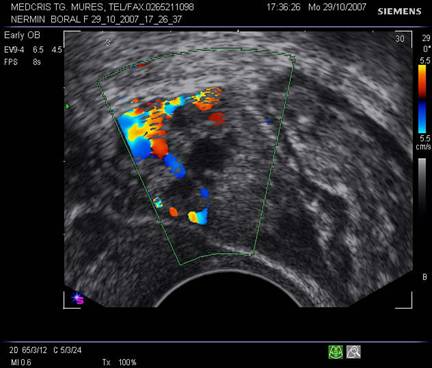

Fig nr 52

Langa ovarul drept ( cu sageata lunga ) se observa o formatiune ovalara cu ecou

hipoecogen central, sarcina extrauterina la 5 sapt. si 3 zile de amenoree ( doua sageti )

Fig nr 53 Aceeasi sarcina extrauterina ca in figura precedenta, se evidentiaza coroana trofoblastica la ecoul doppler color si se schiteaza vezicula vitelina ( cu sageata )